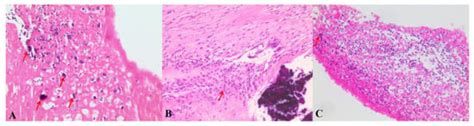

Bartonella Histology